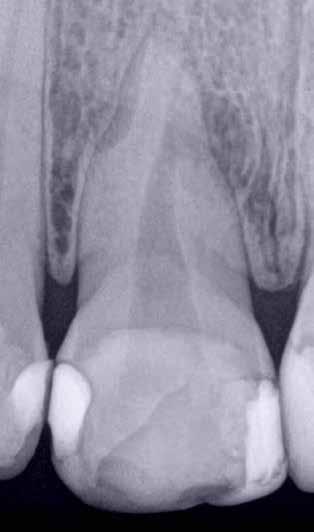

A CBCT-készülékek endodonciai alkalmazásának talán az az egyik legnagyobb előnye, hogy így olyan anatómiai struktúrák is láthatóvá válnak, amelyeket egyébként nem tudnánk detektálni panoráma, cephalo, vagy periapicalis felvételek segítségével. Mivel a CBCT-felvételek kiértékelése számítógép segítségével történik, így a felvételek vizsgálata során lehetőségünk van az adott területet több nézőpontból és több síkban is megvizsgálni. 2015 októberében egy korábban a rendelőnkben kezelt 55 éves férfi páciens azzal a céllal kereste fel ismét a rendelőnket, hogy másodvéleményt kérjen egy jobb felső kvadránsban található fogával kapcsolatban. Egy másik rendelőben történő vizsgálat során a panaszos fog törését vélelmezték és a fog eltávolítását javasolták, illetve arról is beszámolt, hogy az elmúlt hét során ezen a területen egy puha duzzanat is kialakult. A klinikai vizsgálat során a jobb felső első és második kisőrlő között (14–15) egy fluktuáló duzzanatot észleltünk az áthajlásban. Az 15-ös fog mesialis oldalán 12 mm mély tasakot szondáztunk. A páciens által hozott periapicalis felvételen a 15-ös fog gyökércsúcsának mesialis részén egy nagy kiterjedésű radiolucens elváltozás volt észlelhető (1. ábra). A saggitális síkban vizsgált CBCT-felvételen (Carestream CS 9000, Carestream Dental) a lézió valódi kiterjedése is láthatóvá vált (2. ábra). A megelőző endodonciai kezelések során csupán a bukkális csatorna került detektálásra és gyökértöméssel való ellátásra. Az axiális irányú CBCT-szeleteken egyértelműen látható volt az ellátatlan palatinális gyökércsatorna (3. ábra)

Először kalcium-hidroxid alapú ideglenes gyógyszeres zárás került a palatinális csatornába (UltraCal XS, Ultradent Products; 4–5. ábra), amelyet 6 hét után a végleges gyökértömés elkészítése előtt eltávolítottunk. A gyökértömés elkészítése során meleg vertikális kondenzációs technikát alkalmaztunk. Radiológiai felvételen megfigyelhető volt, hogy a gyökértömő anyag egy laterális csatornán keresztül kis mennyiségben a periapicalis térbe extrudálódott (6. ábra). A 4 évvel később készített kontrollfelvételeken a lézió gyógyulása volt megfigyelhető (7–9. ábra). A vizsgálati eredmények és a kezelés kimenetele egyértelműen igazolta, hogy nem gyökérfraktúrával álltunk szemben, tehát a kezdeti diagnózis tévesnek bizonyult. Ez is azt erősíti, hogy korlátozott mennyiségben rendelkezésre álló adatok alapján nem lehet pontos diagnózist felállítani. Manapság szinte elengedhetetlen a CBCT-felvételek endodonciai beavatkozások során történő használata, feltéve, ha ezek elkészítése során az ALARA elv (as low as reasonably achievable) betartásra kerül.